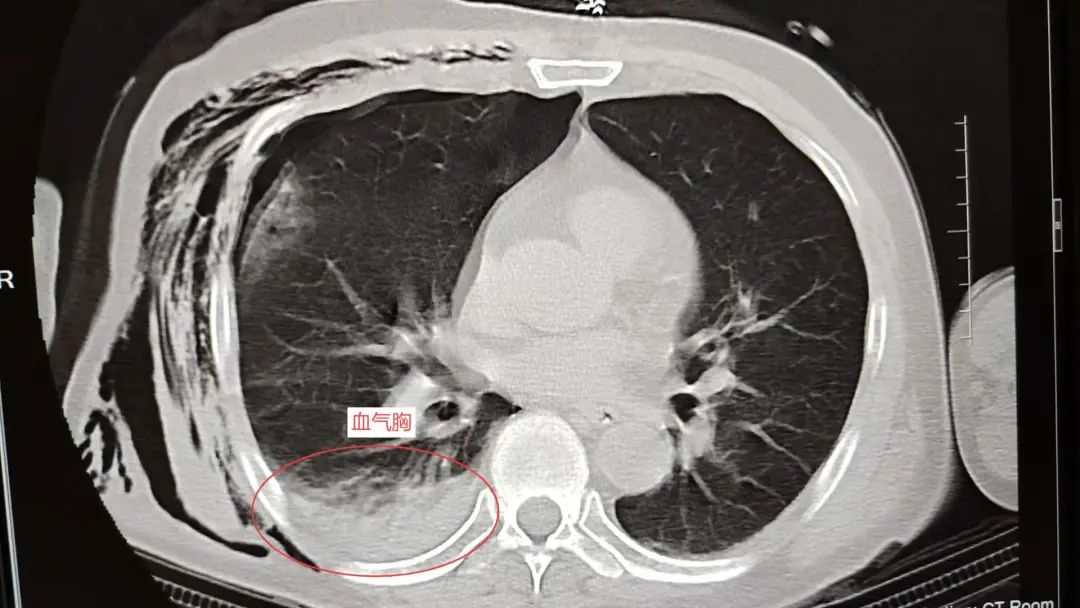

当天10:12,在发现罗叔右侧液气胸加重,并出现呼吸困难,血氧下降情况时,团队迅速响应,进行右侧胸腔闭式引流+右侧皮下气肿引流。

入院时

两小时后的血气胸